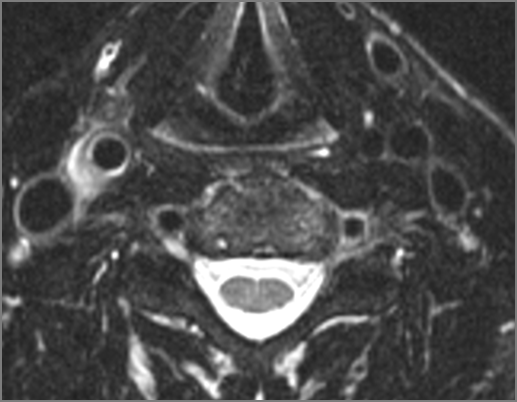

Prevertebral and Epidural Spaces

There is edema/abscess within in the prevertebral or paravertebral spaces.

There is erosive process involving the disc spaces or other components of the spine.